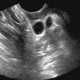

Necrotic lymphadenopathy

Lymphadenopathy or adenopathy is a disease of the lymph nodes, in which they are abnormal in size or consistency. Lymphadenopathy of an inflammatory type (the most common type) is lymphadenitis, producing swollen or enlarged lymph nodes. [Source: Wikipedia ]